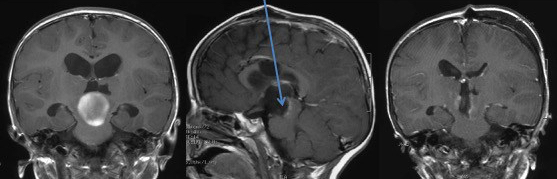

elle a pour buts le diagnostic histo-pathologique, la décompression des structures nerveuses et la libération des voies d’écoulement du LCS, et si possible la cure tumorale. c’est une chirurgical délicate en raison des multiples centres nerveux d’importance vitale, en rapport notamment avec la respiration et l’alimentation (cf. figure ci-contre).

l’abord des lésions du mésencéphale

les voies transcalleuses antérieures (transforaminale ou inter-thalamo-trigonale) sont surtout indiquées pour les tumeurs mésencéphaliques exophytiques vers le troisième ventricule, et lorsqu’il existe une hydrocéphalie.

la voie transcalleuse postérieure peut être indiquée pour des tumeurs tectales développées dans la citerne quadrijumelle. elle est cependant limitée par la lyre du trigone.

la voie sous-occipitale transtentorielle

donne accès à la région pinéale et au tectum mésencéphalique. elle est limitée par l’extension de la tumeur vers l’aqueduc du mésencéphale, ce qui peut nécessiter un deuxième temps par le quatrième ventricule.